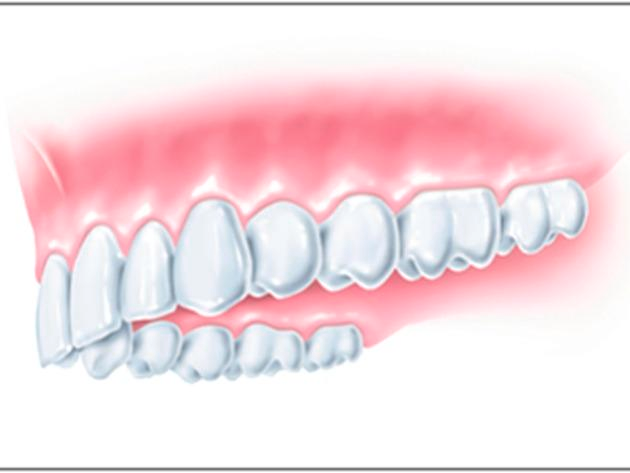

Fest verwurzelt

Der kleine "Pfosten" aus körperneutralem Rein-Titan ersetzt die Zahnwurzel und wächst fest im Kieferknochen ein. Auf diesem Fundament können Zahnkronen, Brücken oder sogar Prothesen fixiert werden. Nach der Versorgung haben Sie wieder den Komfort eines fest verankerten Zahns. Sie verspüren keine Einschränkungen beim Lachen, Sprechen und beim Kauen.

Von der Einzelzahnversorgung bis zum zahnlosen Kiefer können wir Ihnen individuelle Implantatlösungen anbieten, die Ihnen Komfort und Ästhetik auf lange Sicht bringen. Und damit Sie sicher sein können: Bei der Implantologie arbeiten wir eng mit einem der weltweit führenden Implantathersteller zusammen.